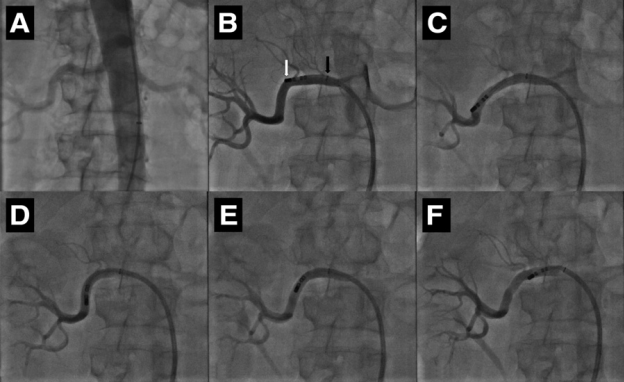

Symplicity HTN-1 (catheter-based renal sympathetic denervation for resistant hypertension: a multicentre safety and proof-of-principle cohort study) là nghiên cứu đầu tiên về tính khả thi, tính an toàn và hiệu quả trên người của phương pháp triệt phá thần kinh giao cảm động mạch thận qua đường ống thông. Nghiên cứu được thực hiện trên nhiều trung tâm tại Australia, 45 bệnh nhân tăng huyết áp kháng trị đã được triệt đốt thần kinh giao cảm động mạch thận hai bên bằng năng lượng sóng tần số radio. Quy trình kỹ thuật trong Symplicity HTN-1: Các bệnh nhân sau khi thỏa mãn các tiêu chuẩn lựa chọn của nghiên cứu sẽ được chuẩn bị cho một thủ thuật thăm dò chảy máu và được chụp động mạch thận chọn lọc qua đường động mạch đùi. Sau đó, một ống thông dẫn (guide catheter) đường kính 8 French sẽ được luồn vào lỗ vào động mạch thận, qua đó, ống thông đốt với kích thước nhỏ hơn sẽ được đưa sâu vào trong động mạch thận để tiến hành triệt đốt thần kinh giao cảm từ phía nội mạch. Ống thông đốt với đặc điểm có thể điều khiển gấp duỗi được bởi bác sĩ thủ thuật (steerable) cho phép triệt đốt thành một đường xoắn ốc vòng quanh lòng động mạch thận từng bên. Cũng tương tự như quy trình triệt đốt các rối loạn nhịp tim bằng năng lượng tần số radio, quá trình đốt mạch thận được kiểm soát bởi các thông số nhiệt độ và điện trở nhằm đảm bảo năng lượng đủ để gây tổn thương mô, cắt đứt các đường dẫn truyền thần kinh giao cảm nhưng không tăng nhiệt độ quá cao gây tổn thương nội mạc làm hẹp động mạch thận. Trong Symplicity HTN-1, có 2 biến chứng liên quan đến thủ thuật được ghi nhận: 1 trường hợp lóc tách nội mạc mạch thận do đầu ống thông đốt. Động mạch thận bị lóc tách sau đó đã được đặt Stent; 1 trường hợp giả phình động mạch đùi do chọc mạch.

Hình 4 : Hình ảnh X quang của kỹ thuật triệt đốt thần kinh giao cảm động mạch thận trong các nghiên cứu Symplicity với ống thông đốt Symplicity®, Flex-Catheter, Medtronic/Ardian Inc. USA